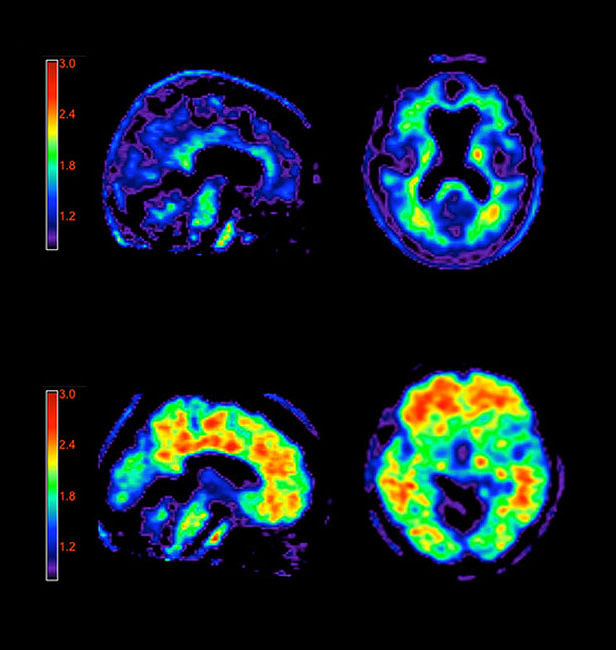

Actualmente, los médicos no pueden saber a ciencia cierta si el cerebro de un paciente está plagado de placas amiloides hasta después de su muerte. Sin embargo, ahora pueden usar un medio de contraste débilmente radiactivo para buscar la presencia de placas en un paciente vivo. Este medio se une a las rígidas placas amiloides que se acumulan en los cerebros de los pacientes de alzhèimer, y pueden ser visualizadas en una tomografía por emisión de positrones (PET, por sus siglas en inglés). La FDA aprobó el escáner como método para estimar el contenido de placas presentes en los cerebros de personas que presentan deterioro cognitivo. La presencia o ausencia de placas en un paciente junto a la falta de memoria, confusión u otros signos de problemas neurológicos podría ayudar a los médicos a realizar sus diagnósticos.

El nuevo medio de contraste, y otros que se utilizan también para analizar la existencia de placas, se ha utilizado en investigaciones clínicas desde hace años, aunque la compañía farmacéutica Eli Lily, cuya filial Avid Radiopharmaceuticals produce el agente de diagnóstico, es la primera en llevar la técnica al consultorio del médico. A algunos expertos les preocupa que el uso clínico del medio de contraste pueda ser un poco prematuro, ya que la presencia de las placas no es suficiente para confirmar el diagnóstico del alzhèimer. De hecho, los depósitos de amiloides se encuentran a menudo en personas mayores con capacidad mental normal y podrían estar asociados con otros trastornos neurológicos. Por ahora, el contraste de Avid solo está aprobado para ser utilizado para descartar la enfermedad (si no se detectan las placas, el médico puede estar seguro de que el paciente no tiene alzhèimer).